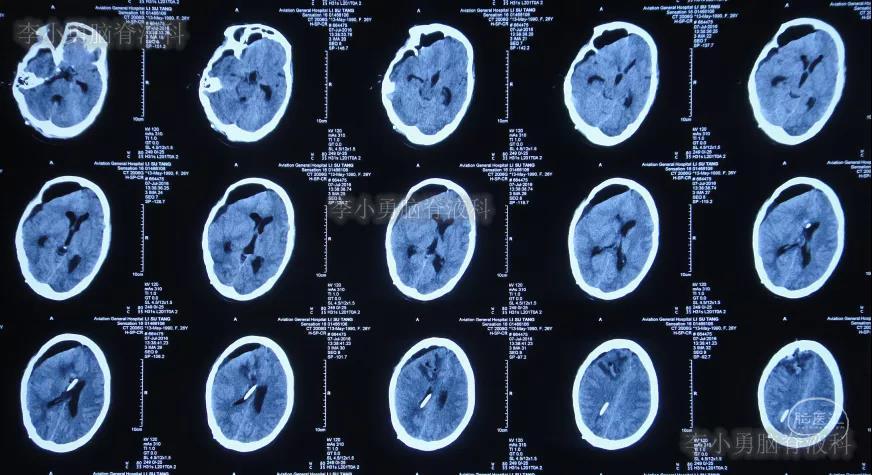

入院治疗209天即2016年11月30日,病情又好转为:意识清楚,能睁眼看电视,但闭眼后再睁眼很慢(图-27),头颅CT示脑积水基本痊愈(图-28)。

图-28:2016年11月30日头颅CT

入院治疗233天即2016年12月24日,头颅CT示脑积水痊愈(图-29)。

图-29:2016年12月24日头颅CT

2017年3月13日(住院10个月),进行了脑室腹腔分流术,术后次日查头颅CT示脑室分流术后状态(图-31)。

图-31:2017年3月13日头颅CT